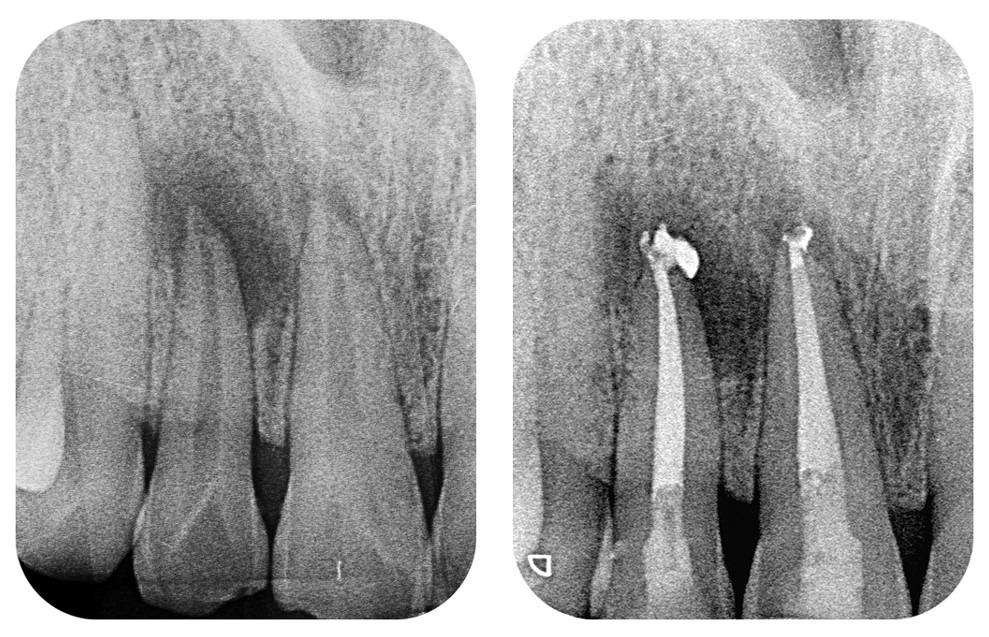

Let’s take a minute to talk about the significance of creating procedure-specific pages. Most premium profile members are quick to set up pages for porcelain veneers, dental implants, and Invisalign®. However, few of them bother setting up pages for root canal treatment or tooth extraction because these treatments rely on X-rays instead of actual photos. This is actually a big mistake. Creating pages for these additional procedures can have a huge impact on your Seach Engine Optimization. You might wonder “what is the point of having X-rays of root canal treatment or tooth extraction since patients don’t care about X-rays”. That may be true, but Google cares and they care a lot! X-rays are the same as photos as far as Google is concerned. Every X-ray that we post to your profile is tagged with your name and procedure name. So when Dr. John Smith sends us 100 before & after X-rays of his root canal treatments, we create an Even28 Root Canal Page that contains 100 X-rays (photos) tagged with Dr. John Smith’s name and the term “root canal treatment”:

• John-Smith-Root-Canal-Treatment-Anterior-before-1

• John-Smith-Root-Canal-Treatment-Anterior-after-1

• John-Smith-Root-Canal-Treatment-Molar-before-1

• John-Smith-Root-Canal-Treatment-Molar-after-1

• John-Smith-Root-Canal-Treatment-Molar-before-2

• John-Smith-Root-Canal-Treatment-Molar-after-2, etc.

Now, imagine Nancy has a toothache and she needs to get a root canal. She searches Google for a root canal specialist in her area and types in “root canal near me” or  “molar root canal” and guess which page she ends up on? We create procedure-specific pages so that Google finds your page when patients are actively searching for those specific procedures. There is no substitute for content, and there is no more powerful place to post your dentistry treatment photos than on Even28! Start gathering your photos and X-rays, and create as many procedure-specific pages as you possibly can. It might take some effort to do this, but we promise, the impact will be nothing short of a miracle.